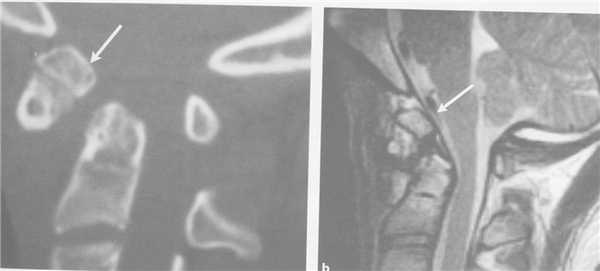

(Слева) Рентгенограмма в боковой проекции: снижение высоты переднего отдела межтелового пространства С6-С7, расширение межостистого промежутка и дистракционное повреждение дугоотростчатых суставов (смещение суставных поверхностей относительно друг друга > 50%).

(Справа) КТ, сагиттальный срез: на уровне боковой колонны шейного отдела позвоночника определяется диастаз и расширение суставной щели суставной пары С6-С7 (> 2 мм), свидетельствующее о наличии связочного повреждения. (Слева) На сагиттальной КТ-ангиограмме у пациента с травмой шейного отдела позвоночника определяется перелом каудо-вентрального угла тела С6. Также здесь виден перелом в области задних элементов позвоночника.

(Справа) Т1-ВИ, сагиттальная проекция: признаки флексионной травмы шейного отдела позвоночника на уровне С6 в виде перелома каудо-вентрального угла тела позвонка и разрыва ППС. В заднем отделе эпидурального пространства видна гематома. (Слева) На сагиттальном Т2 TSE у пациента с флексионным переломом каудо-вентрального угла тела С6 позвонка отмечается патологическое усиление сигнала и нарушение целостности передней покровной пластинки позвонка. Распространенная эпидуральная гематома привела к тяжелой компрессии спинного мозга. Обратите внимание на признаки отека вентральных и дорзальных паравертебральных тканей.

(Справа) Т2-ВИ, сагиттальная проекция: тяжелая флексионная травма шейного отдела позвоночника с подвывихом С5 позвонка, сгибательной деформацией, тяжелым сдавлением спинного мозга и его отеком. Обратите внимание на признаки разрыва задних связок. (Слева) КТ, сагиттальный срез с КУ: пациент с флексионной травмой шейного отдела позвоночника, нижний суставной отросток С6 располагается впереди верхнего суставного отростка С7 Б («сцепившийся вывих»).

(Справа) КТ, аксиальный срез с КУ: пациент с флексионной травмой шейного отдела позвоночника с «сцепившимся вывихом», нижние суставные отростки С6 располагаются впереди верхних суставных отростков С7 (такая рентгенологическая картина носит название признака «обнаженных фасеток» или признака «гамбургера»).